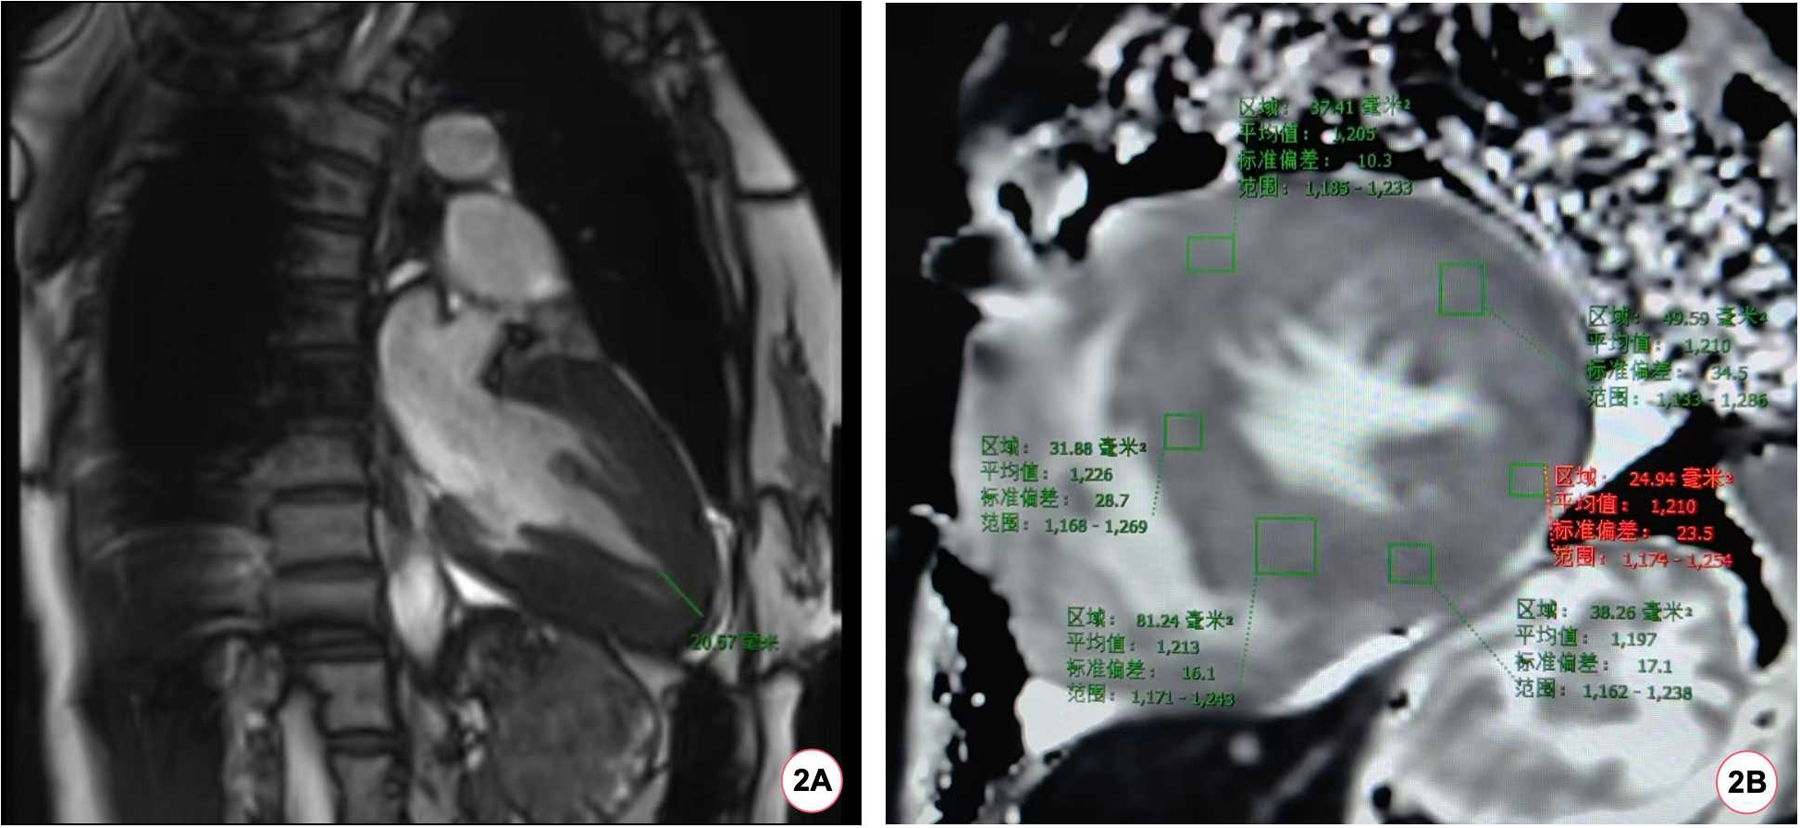

During the hospitalization, Holter displayed an average ventricular rate of 53 bpm and echocardiography showed a left ventricular ejection fraction of 65%, interventricular septal end-diastolic thickness of 15 mm, left ventricular posterior wall end-diastolic thickness of 15 mm, maximum thickness at apex 18 mm without left ventricular outflow obstruction. Cardiac magnetic resonance (CMR) imaging also revealed diffuse hypertrophy in the apical and mid-ventricular walls of the left ventricle, approximately 21 mm in the apical (Figure 2A) and the T1 mapping value was 1,210 ± 23.5 ms (Figure 2B). Ambulatory blood pressure test showed the average 24-hour blood pressure was 120/72 mmHg. Coronary angiography did not show obvious stenosis or slow flow of coronary artery. Considering her recurrent episodes of paroxysmal AF/atrial flutter with obvious symptoms, the patient received bilateral pulmonary vein cryo-ablation, after which it reverted to sinus rhythm (Figure 1D).

Figure 2

The patient's CMR scan. (A) The patient's CMR imaging revealed a ventricular wall thickness exceeding 20 mm at the apex of the heart. (B) The baseline myocardial T1 mapping value of the patient's CMR was 1,210 (±23.5) ms.